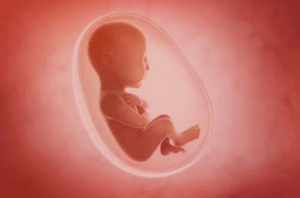

Płyn owodniowy odgrywa bardzo ważną rolę w rozwoju i dobrym samopoczuciu płodu podczas ciąży. Oprócz tego, że jest środkiem ochronnym, przechowuje składniki odżywcze, umożliwia także rozwój układu mięśniowo-szkieletowego płodu, układu pokarmowego i płuc. Przeczytaj nasz artykuł i dowiedz się więcej na jego temat!

Płyn owodniowy to płyn otaczający płód w macicy podczas ciąży. Odgrywa on bardzo ważną rolę we wzroście i rozwoju płodu. W tym artykule odkryjesz kilka bardzo interesujących faktów na temat tej substancji, o których być może niewiele wiedziałeś do tej pory.

Płyn owodniowy odgrywa bardzo ważną rolę w rozwoju i dobrym samopoczuciu płodu podczas ciąży. Oprócz tego, że jest środkiem ochronnym, przechowuje składniki odżywcze i umożliwia rozwój układu mięśniowo-szkieletowego, przewodu pokarmowego i płuc.